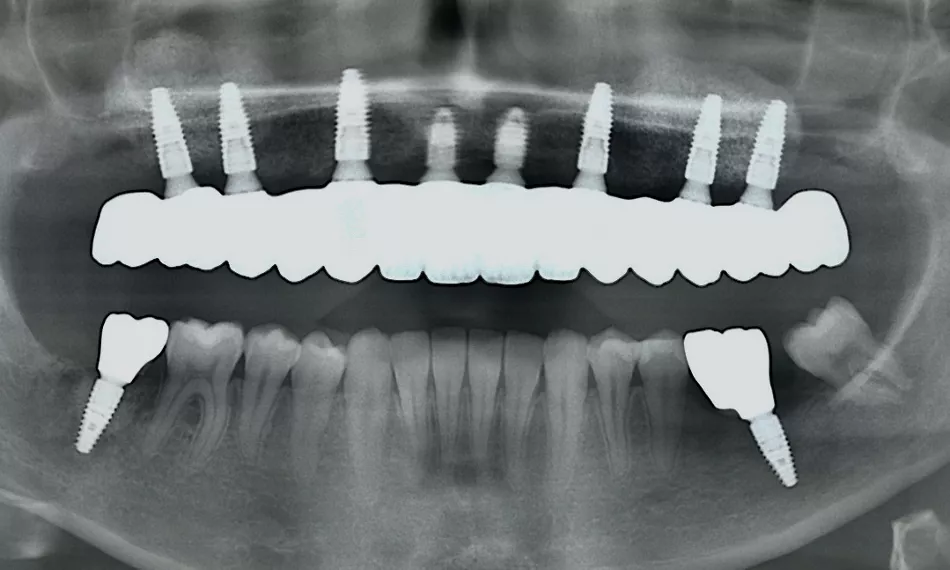

A radiographic control performed one-year post-surgery confirms the successful integration and stability of the implants, providing further evidence of the long-term success of the procedure (Fig. 18). This imaging not only highlights the osseointegration achieved, but also confirms the reliability of the implants in supporting the prosthesis, contributing to the patient's overall dental health.

Fig. 18